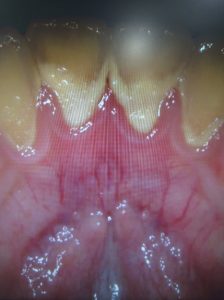

DSC_0071